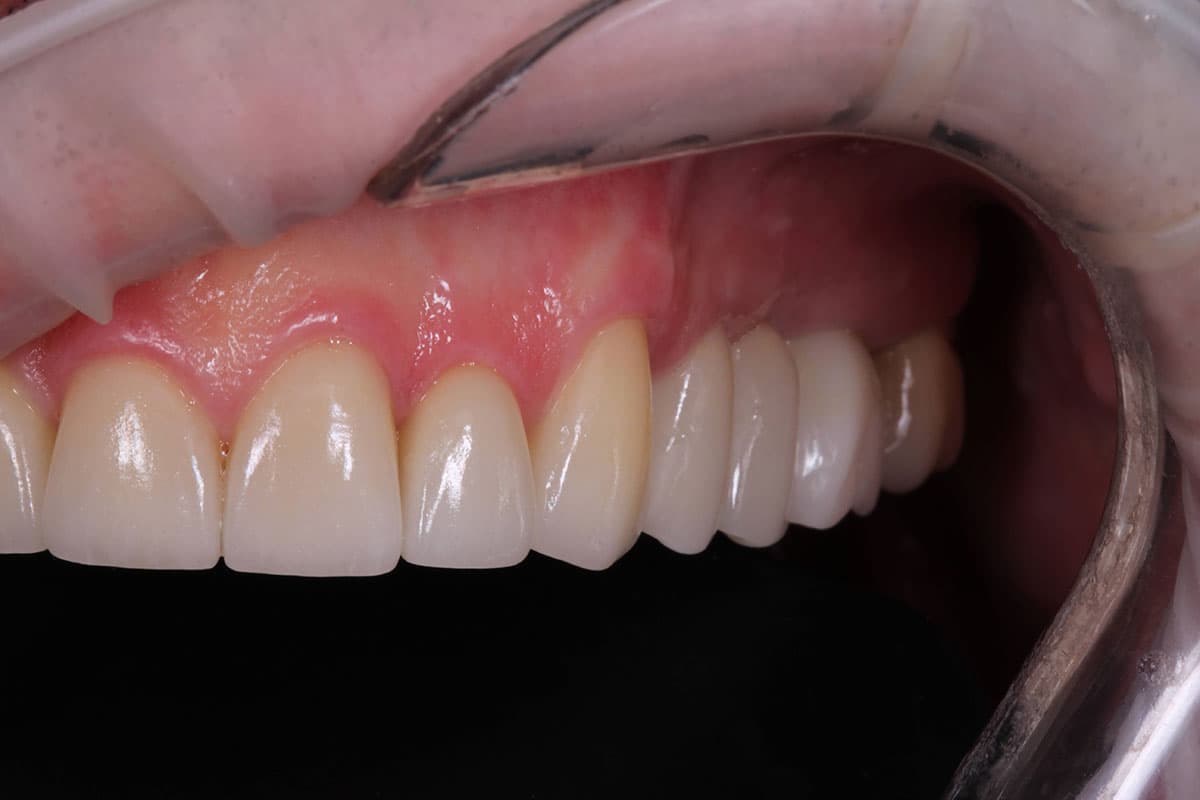

After six months, following digital planning of the future restorations, zirconia crowns and bridge prostheses on implants were placed in the posterior regions, and the worn remaining teeth were restored with ceramic veneers.